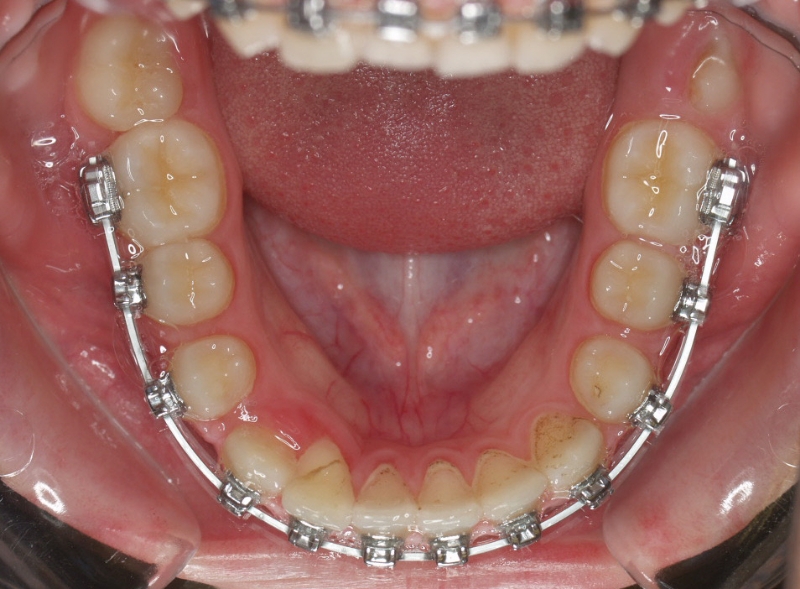

Clase II paciente 15 años

La paciente O.O. acude a nuestra consulta por:

– Canino 13 e incisivo lateral 42 en posición ectópica.

– Canino 23 incluido.

Con lo que decide realizarse un tratamiento de ortodoncia de duración de 24 meses con brackets damon Q.